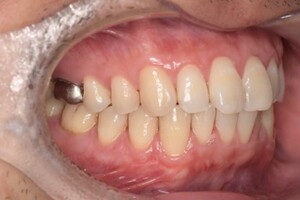

現在の治療費と異なる場合がございます。最新の治療費は料金表をご確認ください。CASE 1

Before

After

基本情報

| 主訴 | 見た目をきれいにしたい |

| 治療期間 | 6ヶ月 |

| 治療費 | ジルコニアボンド(セラミックの被せもの)¥165,000×7(税込み) オフィスホワイトニング4回 ¥4,400×4(税込み) ホームホワイトニング¥11,000 |

| リスク・副作用 | かみ合わせがとても強い方の場合、稀に割れてしまうことがあります。 |

| 先生からの提案 | 上の前歯6本と右下の2番目の歯はセラミックの被せもので治療。 残りの下の前歯5本はプラスチックの材料で虫歯を治療し、 ホワイトニングをおこないました。白くなったご自身の歯の色に合わせてセラミックの 被せものを作成しています。 模型上で完成後をシュミレーションし、上の歯茎の位置をきれいに見えるように 揃えています。(外科処置はしていません) |